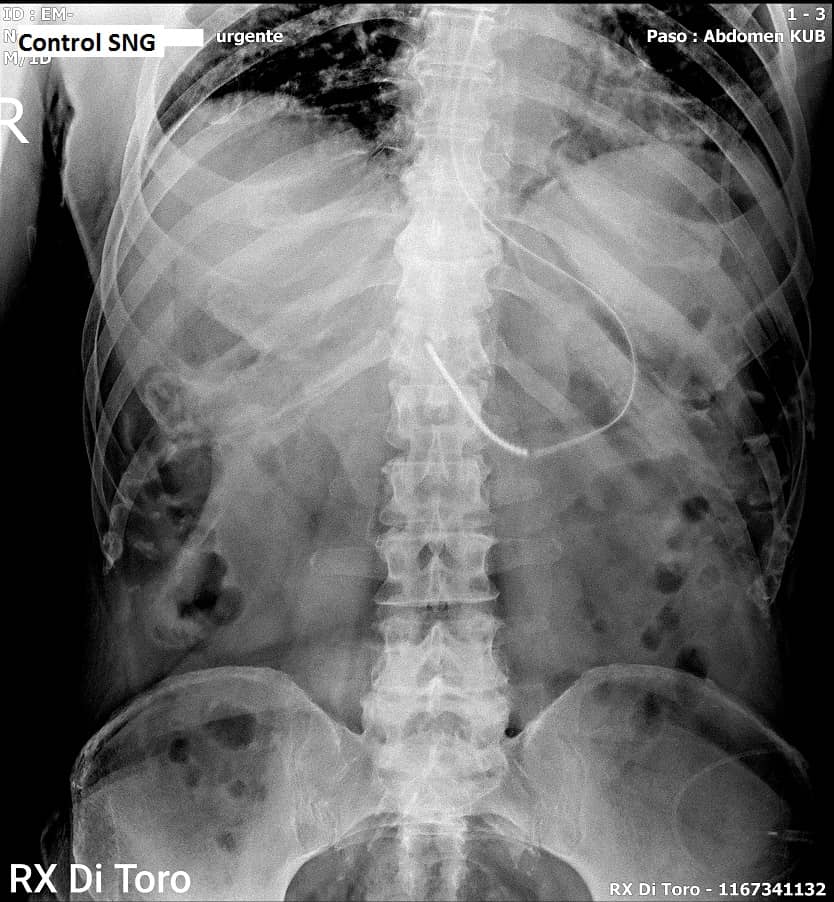

Utilizamos sensores Flat Panel, que nos permiten acortar al Máximo el tiempo de exposición (Dosis de Radiación) y obtener la adquisición inmediata de las imágenes.